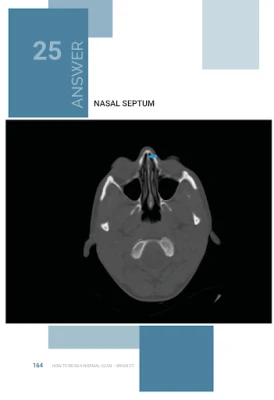

Αυτός ο συναρπαστικός και εύχρηστος Άτλας / Κουίζ Φυσιολογικής Νευροακτινολογίας γεφυρώνει το χάσμα μεταξύ ανατομικών και ακτινολογικών άτλαντων. Εστιάζει στις ανάγκες ειδικευόμενων νευρολόγων και φοιτητών ιατρικής, προσφέροντας παράλληλα πολύτιμες γνώσεις σε όποιον ενδιαφέρεται για την ακτινολογική ανατομία του εγκεφάλου.

Η σειρά "How to Read a Normal Scan", γνωστή και ως "Normal Radiology", σχεδιάστηκε ακριβώς για να καλύψει αυτό το κενό. Ο πρωταρχικός της στόχος είναι να σας εξοικειώσει πλήρως με τη ΦΥΣΙΟΛΟΓΙΚΗ ανατομία, όπως αυτή εμφανίζεται σε σαρώσεις MRI και CT. Αντί να προσπαθείτε να απομνημονεύσετε σπάνιες παθήσεις, αυτή η εκπαιδευτική πηγή σας δίνει τα απαραίτητα εργαλεία για να αναγνωρίζετε με ακρίβεια τις δομές σε μια κανονική σάρωση. Πρόκειται για την ικανοποίηση του να γνωρίζεις, όχι μόνο για την αποφυγή της αμηχανίας. Με μια σταθερή βάση στη φυσιολογική ανατομία, θα είστε εξοπλισμένοι για να προχωρήσετε με σιγουριά στην πολυπλοκότητα της διάγνωσης.